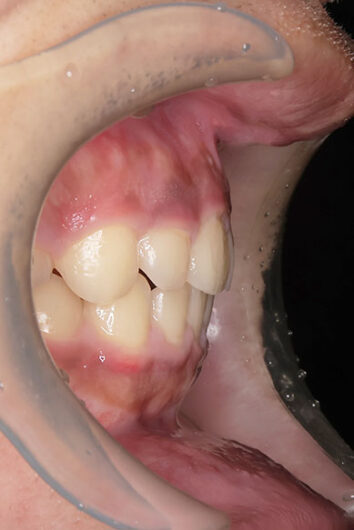

右上の前歯が生えてこない事を気にされ来院されました。 レントゲン写真から、上顎正中に過剰歯が埋伏していることが原因でしたので、抜歯して経過観察。 遅れて、無事に生えてきました。 もし、自然に生えてこない場合は、開窓して、引っぱり出します。(廷出) 状態により、引っぱり出せない場合もあります。 将来的にスペース不足により、上下顎前臼歯部に重度の叢生(がたつき)が予測できますので、がたつきを減らすために、小児矯正で側方拡大を行いました。 小児矯正で側方拡大を行ってもスペースが足りない場合(著しくスペース不足の場合)は、がたつき(叢生、八重歯)が残ります。 残ったがたつき(叢生)は、本格矯正ですべて生え変わった中学生から治せば問題ありません。 来院間隔が平均で1.5カ月でしたので半年ほど治療期間が長いです。